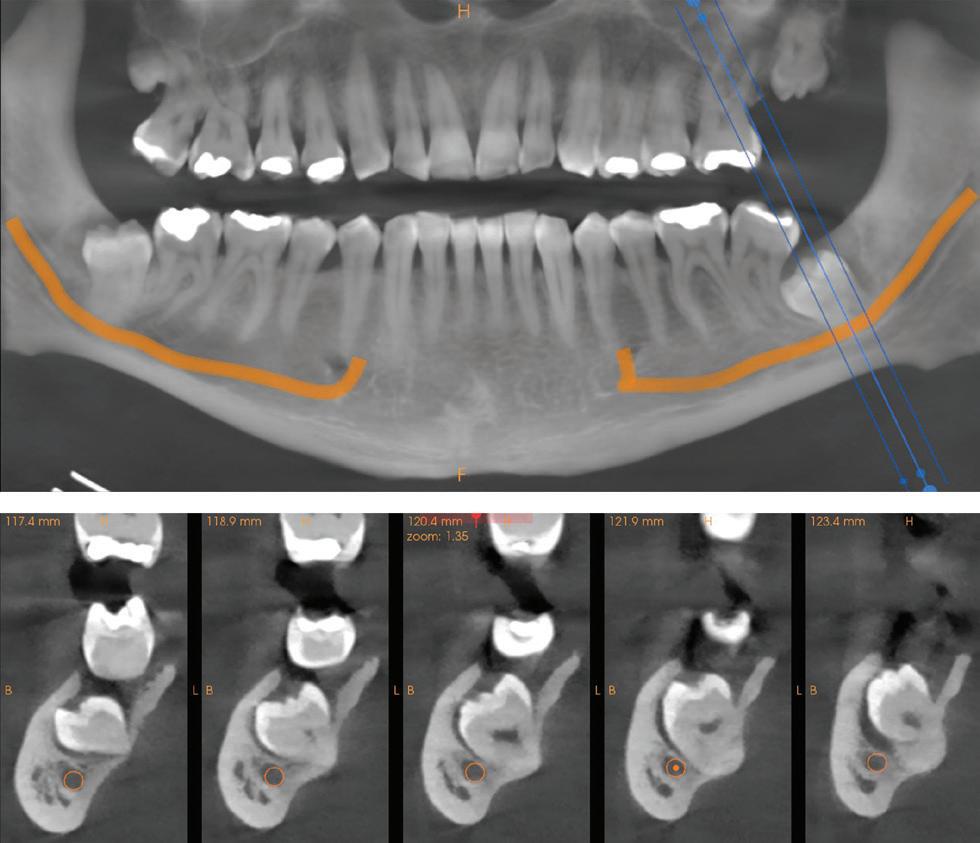

Figure 1: Radiographic Image of implants do not demonstrate bone loss due to the bisecting angle of the radiograph taken.

Figure 2: Radiographic image in a paralleling technique of implants dem onstrate moderate peri-implantitis with bone loss that will necessitate treatment.